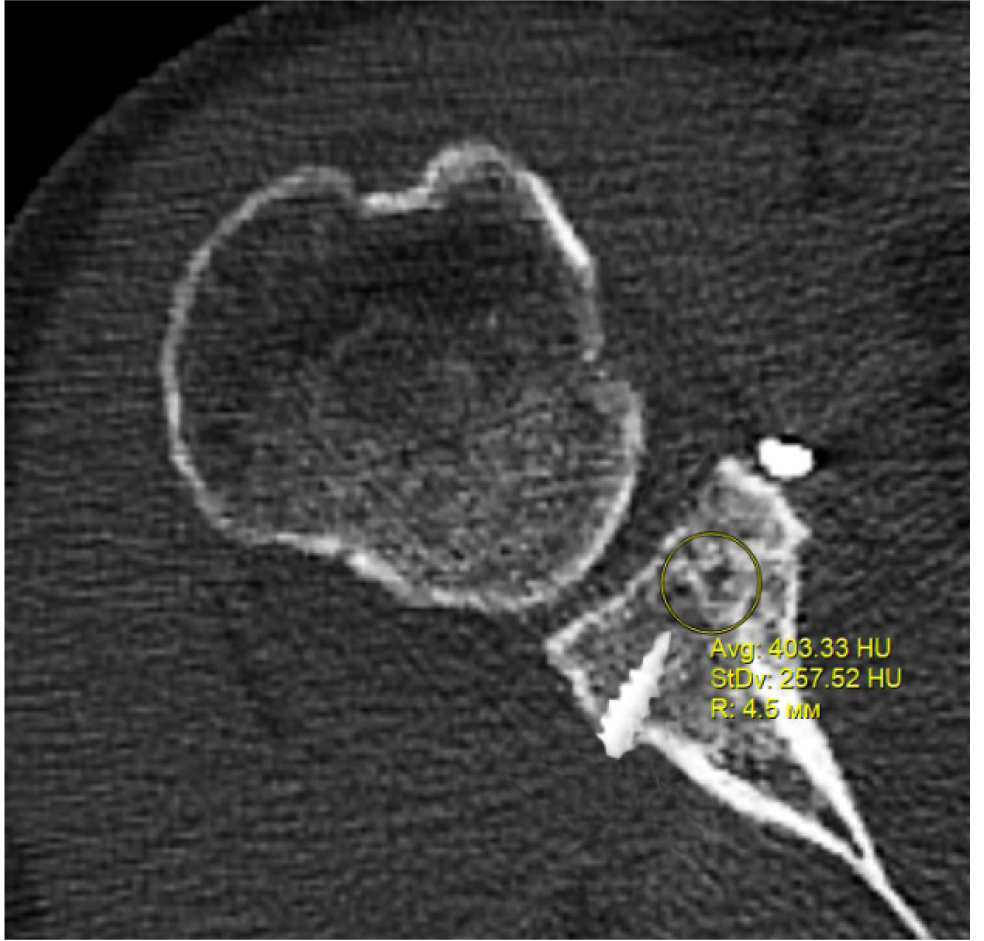

В программном обеспечении, на аксиальных КТ срезах оперированного плечевого сустава, выбирали инструмент «круг», который позволял посчитать среднюю плотность тканей внутри круга в единицах Хаунсфильда. Шкала единиц Хаунс-филда (HU) – шкалалинейного ослабления излучения по отношению к дистиллированной воде, рентгеновская плотность которой была принята за 0 HU (при стандартных давлении и температуре). Круг устанавливали таким образом, чтобы одна его половина была заполнена тканью гленоида, вторая половина тканью трансплантата (рис. 1–3). Оценивали плотность тканей над проксимальным винтом, между винтами, под дистальным винтом. Полученные данные анализировали с помощью пакета Microsoft Excel.

Рис. 2. Оценка плотности ткани между винтами

Через 3 месяца после оперативного лечения по данным анализа КТ срезов были получены следующие результаты: плотность ткани над проксимальным винтом составили (424 ± 24,3) HU, между винтами (460 ± 23,4) HU, под дистальным винтом (587 ± 49,1) HU. Спустя 6 месяцев после операции плотность ткани над проксимальным винтом составили (320 ± 28,7) HU, между винтами (424 ± 36,2) HU, под дистальным винтом (623 ± 33,4) HU. Через 12 месяцев после операции показатели были следующие над проксимальным винтом (276 ± 22,1) HU, между винтами (387 ± 31,1) HU, под дистальным винтом (662 ± 43,2) HU (таблица).

Между винтами | 460,0 ± 23,4 | 424,0 ± 36,2 | 387,0 ± 31,1 |